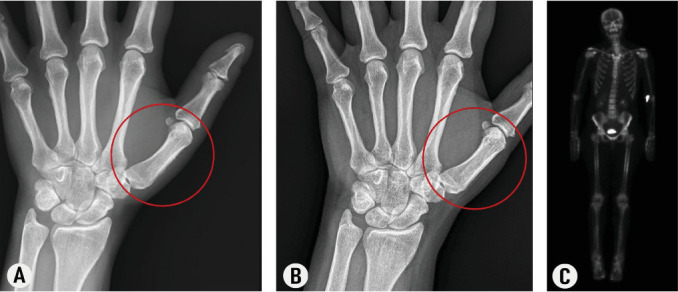

Graves病是一种自身免疫性甲状腺病,伴有甲状腺功能亢进和非内分泌表现,如甲状腺眼病(TED)、胫前黏液水肿和甲状腺粗肿。甲状腺肢肿是一种不常见但使人衰弱的疾病,典型的特征是手指杵状,软组织肿胀,以及手和脚的骨膜新骨形成。这种情况通常伴随着TED和皮肤病,但有效的治疗方法仍然难以捉摸。teprotumumab是一种靶向胰岛素样生长因子-1受体(IGF-1R)的单克隆抗体。一名49岁女性,有格雷夫斯病病史,出现严重的肌肉骨骼症状,包括棒状和骨膜新骨形成。尽管最初使用利妥昔单抗和静脉注射免疫球蛋白的治疗效果有限,但主要用于TED的teprotumumab治疗导致了显着的临床和放射学改善。在完成8个疗程的teprotumumab治疗后,患者的肌肉骨骼疼痛缓解,棒化消退,骨膜骨形成的影像学表现减少。该病例强调了teprotumumab作为甲状腺粗肿的新治疗选择的潜力,并表明IGF-1R在其发病机制中起关键作用。虽然该报告显示了令人鼓舞的结果,但需要进一步的研究来证实teprotumumab治疗甲状腺粗肿的疗效,并更好地了解其对这种罕见疾病的长期影响。

Graves' disease is an autoimmune thyroidopathy associated with hyperthyroidism and nonendocrine manifestations such as thyroid eye disease (TED), pretibial myxedema, and thyroid acropachy. Thyroid acropachy is an uncommon but debilitating condition, typically characterized by digital clubbing, soft tissue swelling, and periosteal new bone formation in the hands and feet. This condition often accompanies TED and dermopathy, but effective treatments remain elusive. The first documented case of thyroid acropachy successfully treated with teprotumumab, a monoclonal antibody targeting the insulin-like growth factor-1 receptor (IGF-1R), is reported here. A 49-year-old female with a history of Graves' disease developed severe musculoskeletal symptoms, including clubbing and periosteal new bone formation. Despite initial therapies with rituximab and intravenous immunoglobulin showing limited benefit, treatment with teprotumumab, primarily prescribed for TED, led to significant clinical and radiological improvement. After completing eight cycles of teprotumumab, the patient's musculoskeletal pain resolved, clubbing regressed, and radiologic findings of periosteal bone formation diminished. This case highlights the potential of teprotumumab as a novel therapeutic option for thyroid acropachy and suggests that IGF-1R plays a crucial role in its pathogenesis. While this report presents promising results, further studies are needed to confirm the efficacy of teprotumumab in treating thyroid acropachy and better understand its long-term effects on this rare condition.